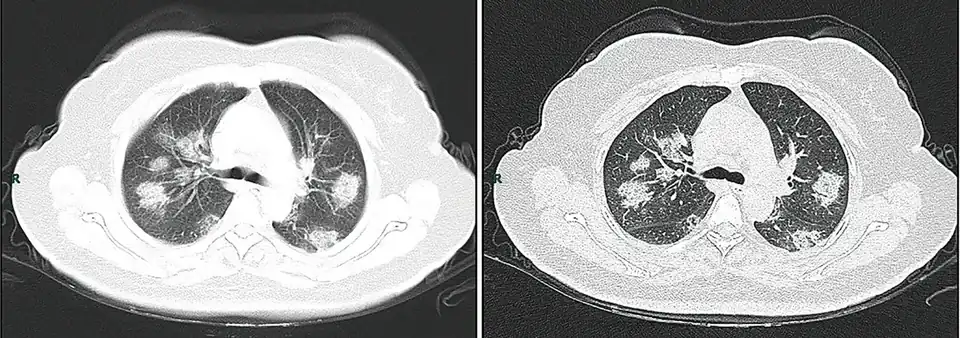

- ↑ Billedbeskrivelse på Commons : "CT imaging of rapid progression stage. A 50 years old female with anorexia, fatigue, muscle soreness, nasal congestion and runny nose for 1 week, sore and itching throat for 2 days. Laboratory test: increased erythrocyte sedimentation rate (25 mm/h), normal white blood cells (4.08 × 109/L), decreased lymphocytes (0.96 × 109/ L), increased C-reaction protein (60.8 mg/L). Imaging examination: a (thin layer CT) and b (high-resolution CT) showed multiple patchy and light consolidation in both lungs and grid-like thickness of interlobular septa"